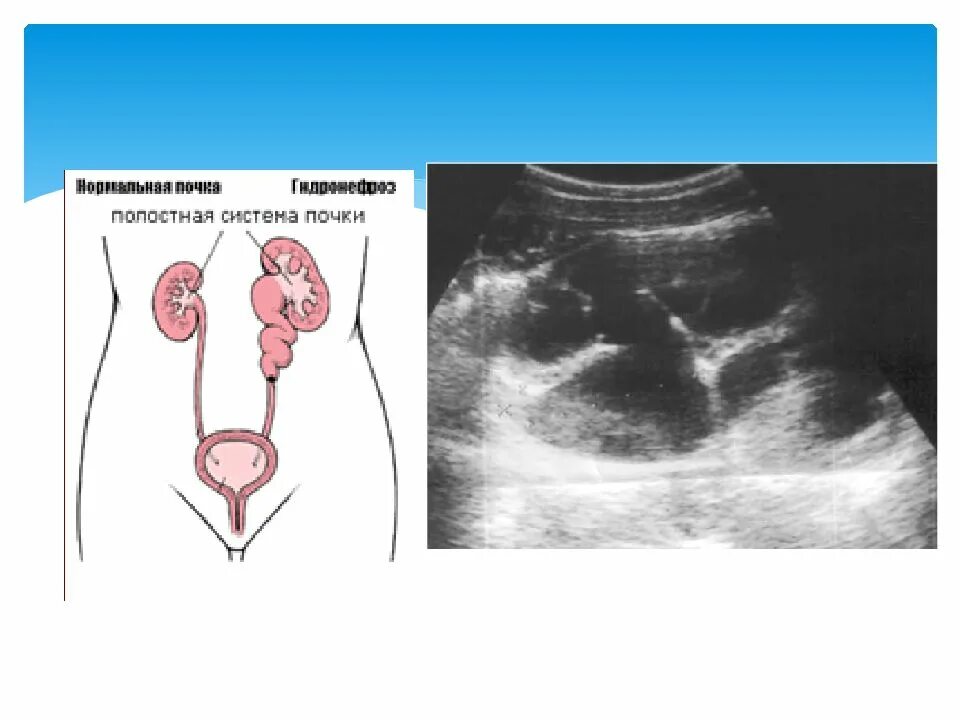

Гидронефроз 1 степени